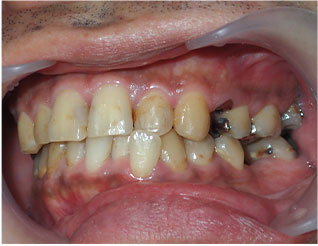

- ブリッジ 症例写真 B-0103オールセラミッククラウン8本 男性モニターの方です。

Before

After詳細はコチラ

オールセラミッククラウン法によるブリッジ治療の症例

施術 オールセラミッククラウン8本 - コメント

この方は小臼歯に欠損がありました。 また、虫歯治療痕が変色していたり、虫歯になっている歯もありました。 歯並びを整えて白くしたいとというご希望もありましたので セラミック法で歯並びを治し、欠損部分はブリッジで治しました。 セラミックの色は患者様のお好みの白さでお作り致しました。 治療回数は6回でした。